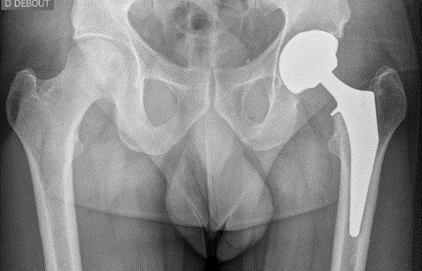

Destruction progressive du cartilage de l'articulation coxo-fémorale. Principale cause de remplacement prothétique de la hanche, elle entraîne douleurs mécaniques, raideur et limitation fonctionnelle.

Prothèse totale de hanche (PTH)

Arthrose avancée de la hanche avec cartilage irrémédiablement détruit.

L'opération

Incision à l'avant de la hanche, les muscles sont simplement écartés (non coupés), ce qui assure une très bonne stabilité et une récupération rapide. Aucun mouvement interdit après l'opération. Durée : 1 heure. Hospitalisation : 0 à 2 jours.

Hématome, infection (< 1 %), luxation de prothèse (< 1 %), phlébite, lésion nerveuse.

Résultats attendus

Disparition rapide des douleurs. Durée de vie : 20 à 25 ans. Vélo, natation, golf autorisés.

Pourquoi opérer ?

Même indication que la voie antérieure : arthrose de hanche avancée.

Incision à l'arrière de la hanche, technique la plus utilisée au monde. Certains muscles sont coupés puis réparés. Excellente exposition chirurgicale, adaptée aux hanches complexes, reprises prothétiques ou patients obèses. Durée : 1 heure. Hospitalisation : 1 à 3 jours.

Identiques à la voie antérieure : hématome, infection (< 1 %), luxation (< 1 %), phlébite, lésion nerveuse.

Identiques à la voie antérieure. Durée de vie : 20 à 25 ans.

La PTH est l'une des interventions chirurgicales les plus efficaces et les plus étudiées en orthopédie. Elle restaure une articulation indolore avec une durée de vie implantaire de 15 à 20 ans en moyenne.

Le choix de la voie d'abord (postérieure, antérieure de Hueter, ou de Röttinger) et du type d'implant (cimenté, non cimenté, hybride) est individualisé selon l'anatomie, l'âge et l'activité du patient.

Le protocole de Récupération Améliorée Après Chirurgie (RAAC) permet une mise en charge dès le jour de la chirurgie et un retour à domicile accéléré.